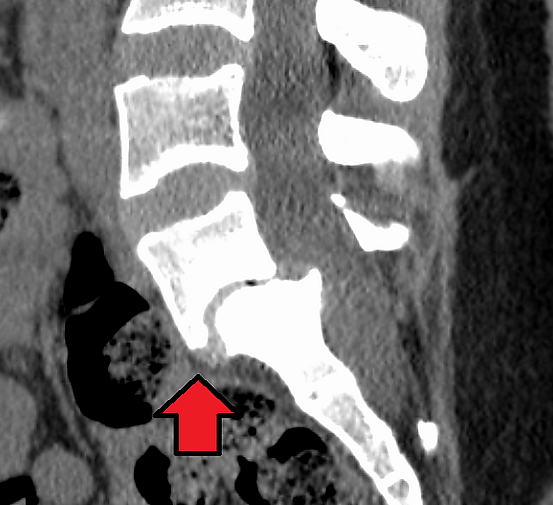

Диагностика

1. Консультация невролога, хирурга-вертебролога

2. МРТ позвоночника

3. Электромиография